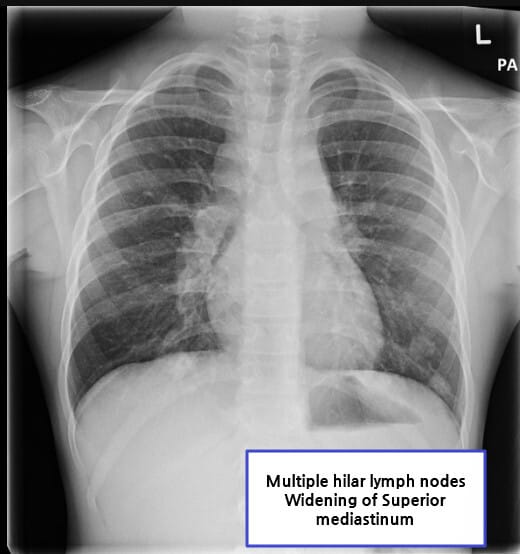

| 경부, 쇄골상, 종격동 림프절이 단단하고 고정되지 않으며 점진적으로 커집니다. |

림프절 생검을 통해 확진하며, 영상 검사로 병기 설정을 진행합니다.

Kirby A, Hodgkin lymphoma. Case study, Radiopaedia.org (Accessed on 18 Jul 2025) https://doi.org/10.53347/rID-151561